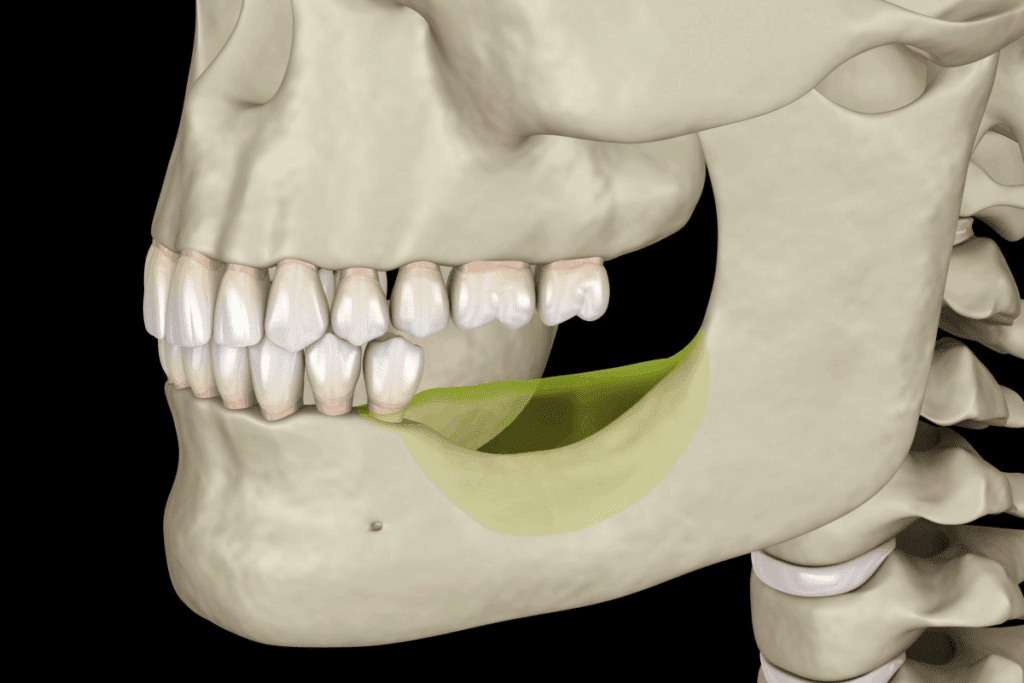

Knowing how the jaw works is key to figuring out pain. The jaw has many parts, like the TMJ, muscles, and tissues. Problems in these areas can cause pain, often on one side.

Structure of the Jaw and Surrounding Tissues

The TMJ links the jawbone to the skull. It’s vital for moving the jaw, letting us talk, chew, and yawn. The jawbone, or mandible, meets the skull at the TMJ. This joint is wrapped in muscles, ligaments, and tissues that help it move.

The temporomandibular joint is special. It moves like a hinge and slides, making it very complex.